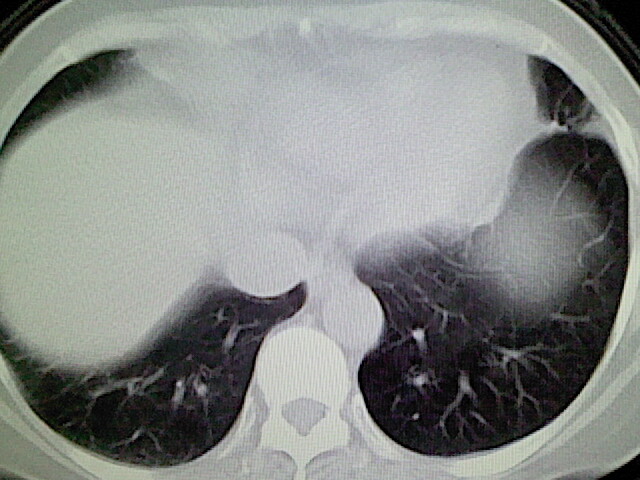

女,52岁,咳嗽,咳痰多日

左下肺陈旧纤维索条!

左肺舌段炎性改变

我见过几例,为炎症后纤维条索

慢性炎症后改变

考虑慢性炎性病灶粘连牵拉改变。

左肺舌叶纤维锁条病变。

左肺上叶下舌段炎症并局部胸膜反应。

左肺舌叶纤维索条影。

左肺舌叶段陈旧性病变

左肺舌段炎性反应。片子的质量太不好了。

左肺舌段炎性

炎性改变

左肺舌叶纤维索条影